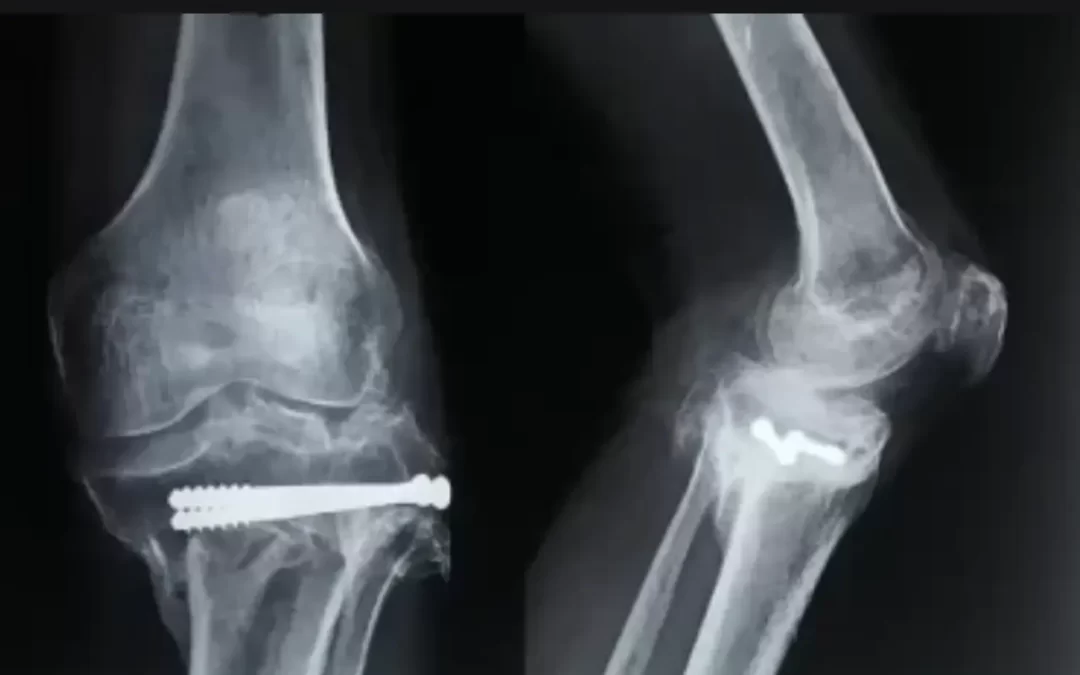

Total Knee Replacement (TKR) Using Stryker Triathlon System

by Dr. Chetan Nagaraj | Apr 8, 2022 | Knee Replacement

Dr Chethan has performed successfully Total Knee Replacement using Stryker Triathlon System A 47-year-old patient had sustained a fracture of his leg bone (tibia) 10 years ago which was treated elsewhere with surgery. Although his fracture had healed, it had healed in...